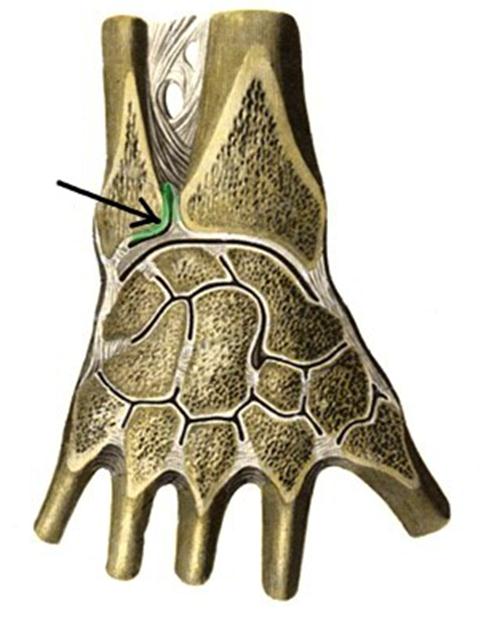

S: Стрелка указывает на art. ### (латинский язык).

+:humeri

+:Humeri